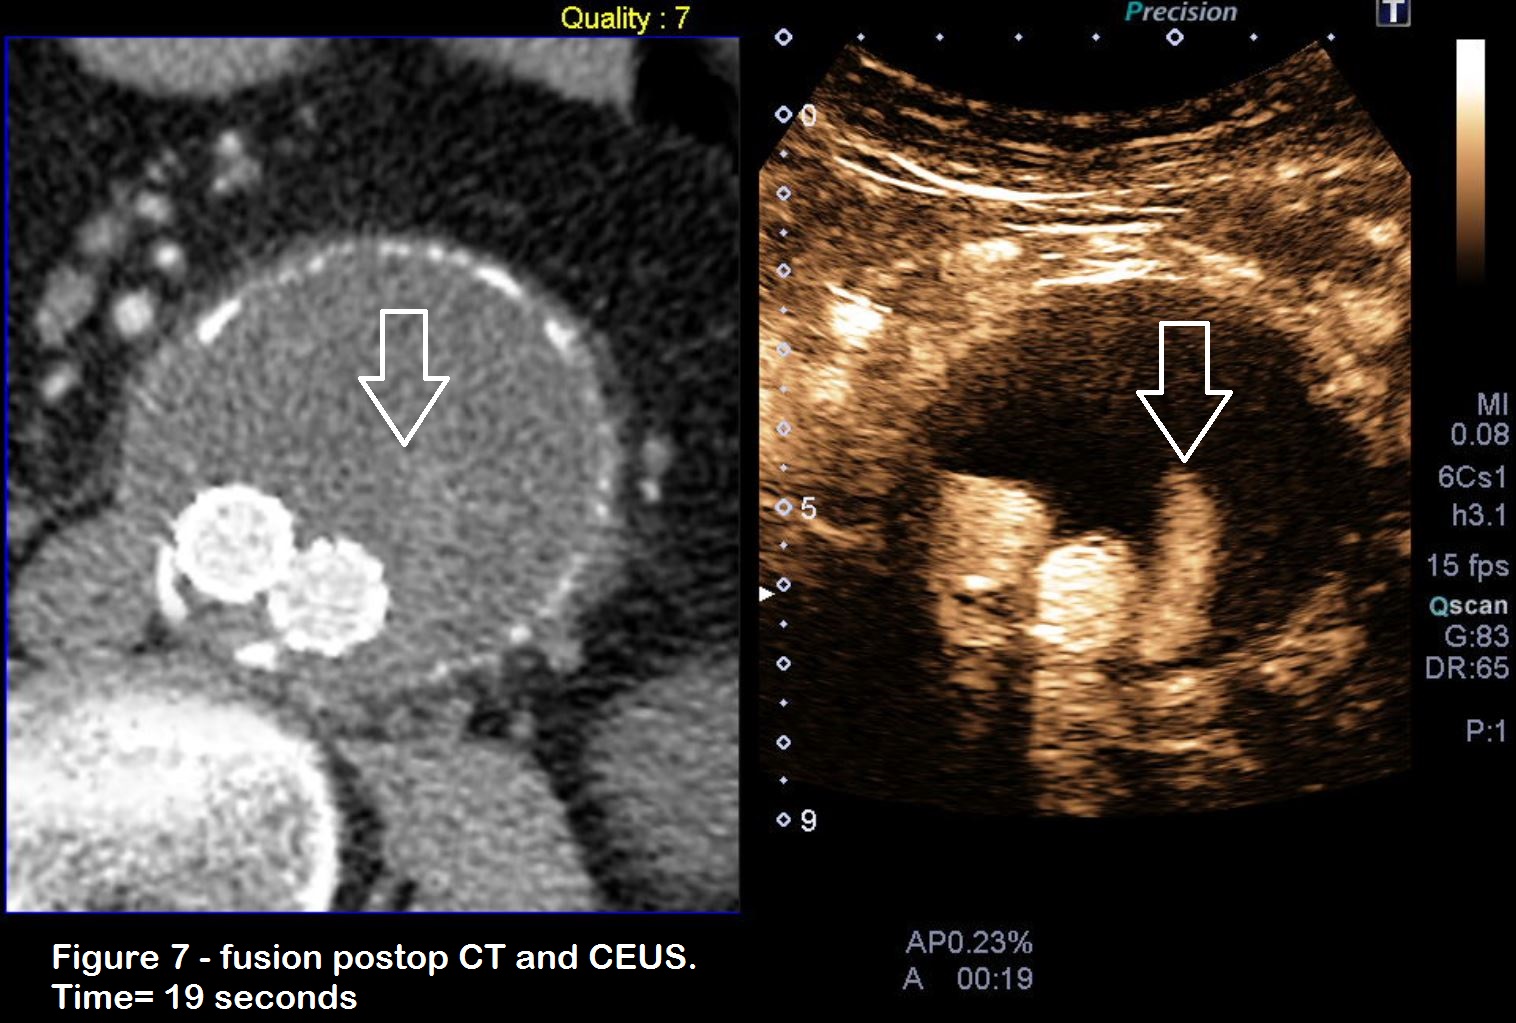

Figures 6 & 7: Two further injections of contrast with images focused lower down in the stent graft, where there was Doppler flow in the stent. Note the time difference where the first passage of contrast through the graft (figure 6) occurs at 10 seconds after injection, but the endoleakage only appears after 19 seconds. There is thus a delay of nine seconds which is a strong indicator that this is a type 2 endoleak. (time is shown at the bottom of the picture, A = seconds after injection).